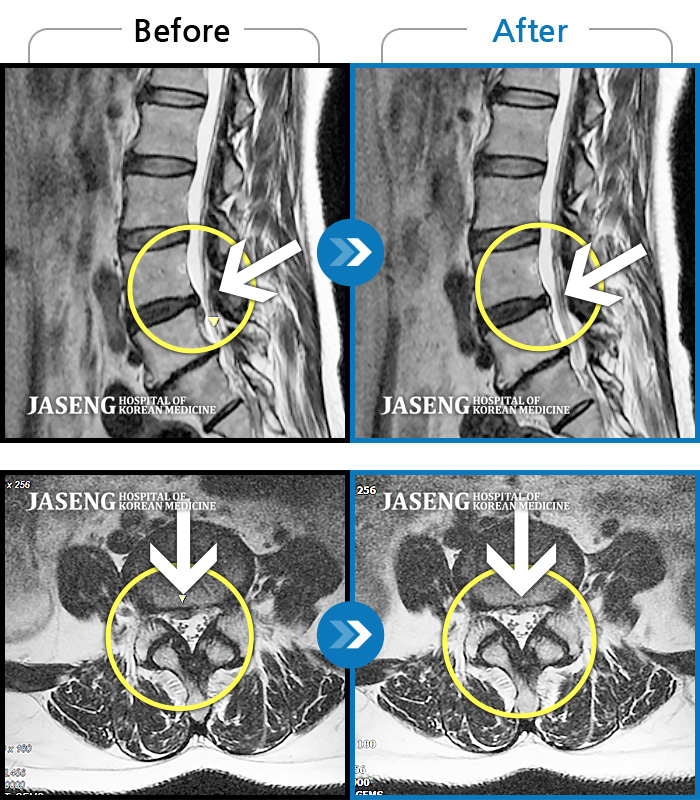

Before

After

환자에게 사전 동의를 받아 동일 조건에서 촬영되었습니다.

개인에 따라 치료 후 부작용이 발생할 수 있으니 의료진과 상담 후 치료를 진행하시기 바랍니다.

우측 허리와 골반 통증, 우측 다리에 통증과 저림

허리디스크로 옆으로 쪼그려 누워서 내원